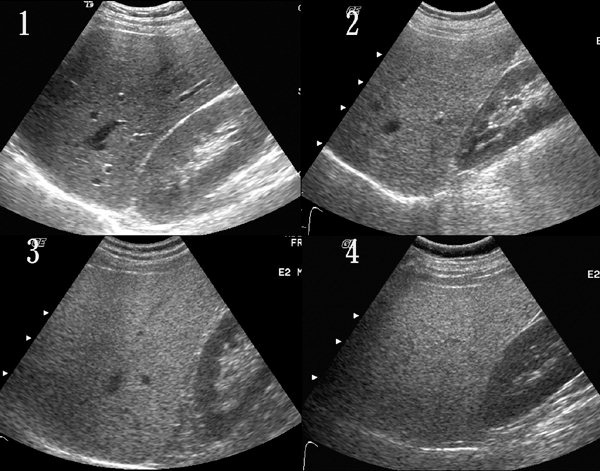

🚨 지방간이 무서운 이유

초기엔 증상이 거의 없음

👉 그래서 더 위험

진행되면👇

❗ 지방간 → 간염

❗ 간경변

❗ 간암까지

👉 조용히 진행되는 “침묵의 질환”